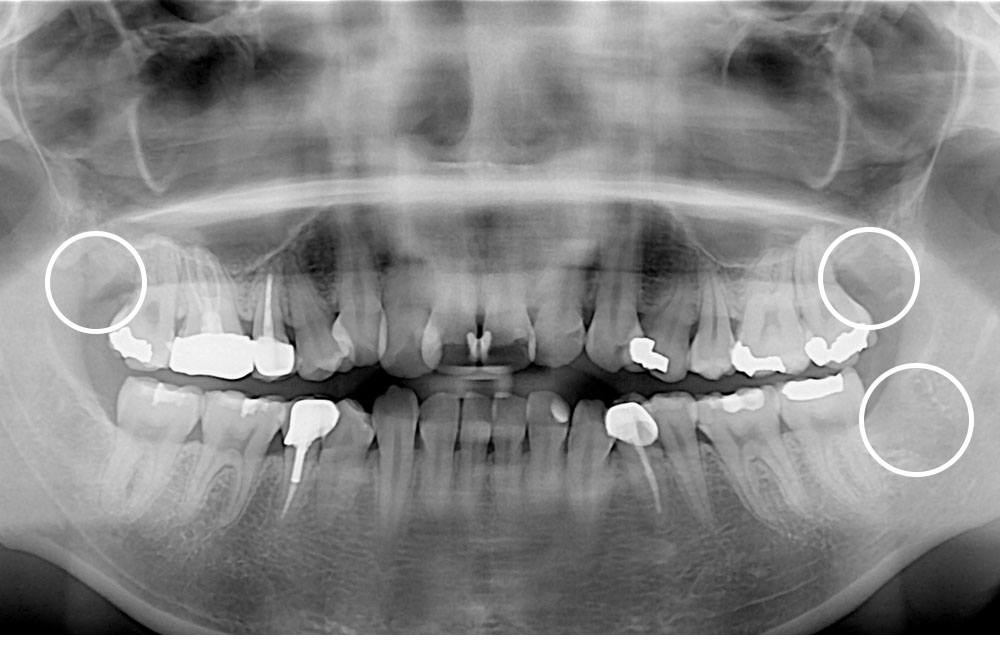

[사랑니] 매복 사랑니 발치

치료전 : 2017-09-26